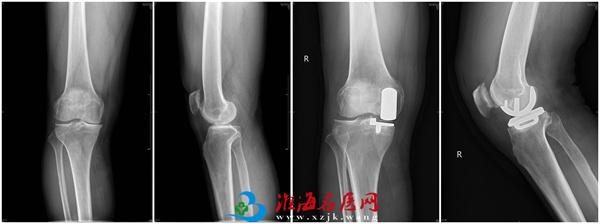

近日,在院领导的关心和支持下,在骨关节科、手术室的配合下,医院骨关节科卢文海、史思峰及孙少松医师成功为一位膝关节骨性关节炎患者实施了全生物型牛津单髁膝关节置换术。该手术为膝关节单髁置换手术中的一种新的方式,为医院首次采用,为医院骨关节科在膝关节单髁置换技术方面又增加了一项新的内容。

来自安徽宿州的患者王先生,因为膝关节疼痛3余年、加重1年入院,诊断为“右膝关节骨性关节炎”,患者右侧膝关节内翻畸形,内侧间隙疼痛明显,无法自主蹲起及长距离行走。经骨关节科医师讨论认为:患者病痛位于膝关节内侧,内侧间室的软骨破坏明显,具备内侧单髁置换手术指征,无手术禁忌症,于2021年7月15日在卢文海副主任医师、史思峰副主任医师、孙少松主治医师协作配合下进行了右膝关节内侧全生物型单髁置换术。手术顺利。术后第二天患者即可自行下地行走,术后功能恢复良好。7月20日,王先生出院。8月27日,他来院复查时,自己行走自如,屈伸活动良好。

卢文海副主任医师介绍,膝关节单髁置换相对于全膝关节置换而言是一种微创术式。只对膝关节内侧或外侧间室进行表面置换,不需要去除膝关节内的前后交叉韧带,最大限度的保留了患者的本体感觉和关节功能,具有创伤小、疼痛轻、恢复快的优点。而生物型牛津单髁膝关节置换术(Cementless Oxford Unicompartmental Knee Arthroplasty,COUKA)自2004 年由牛津大学首创以来,国外临床应用较多,但在国内起步较晚。使用生物型牛津单髁膝关节假体可避免骨水泥相关并发症,缩短手术时间;减少透亮线,以期望降低翻修率。不过生物型牛津单髁假体的使用要严格掌握适应症,对于骨质疏松、局部骨坏死、术后活动较大、髁畸形等患者要慎重选择。